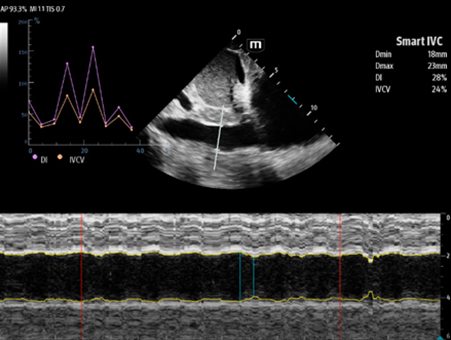

MindrayŌĆśs critical Ultrasound solutions drive improvements in care quality. Integrating advanced hemodynamic Ultrasound features, we can guarantee the highest standard of clinical care. The unique interoperability of Ultrasound and Vital sign data, we can provide comprehensive patient status data, to help inform clinical decisions, enhance clinical efficiency and, ultimately, improve patient outcomes.